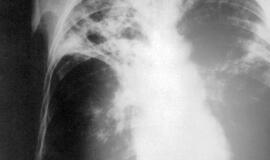

tuberkuliozė

Rentgeno nuotrauka, plaučiai